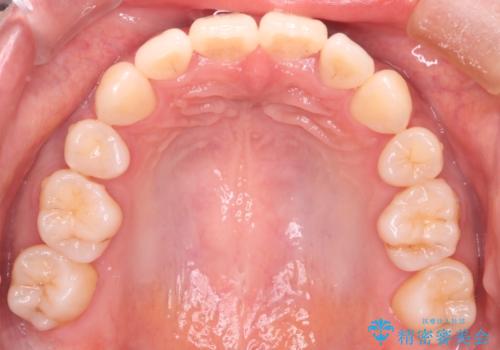

【審美装置】前歯のデコボコを綺麗に

- 上の前歯のデコボコが気になるということで来院されました。

叢生量(デコボコ)が多いため、上下左右4番目の歯を抜歯してワイヤー矯正を行う治療計画を立てました。

主訴である前歯のデコボコが改善され、噛みあわせも綺麗になりました。

歯肉退縮もなく、予定通りに治療を終えることができ良かったです。